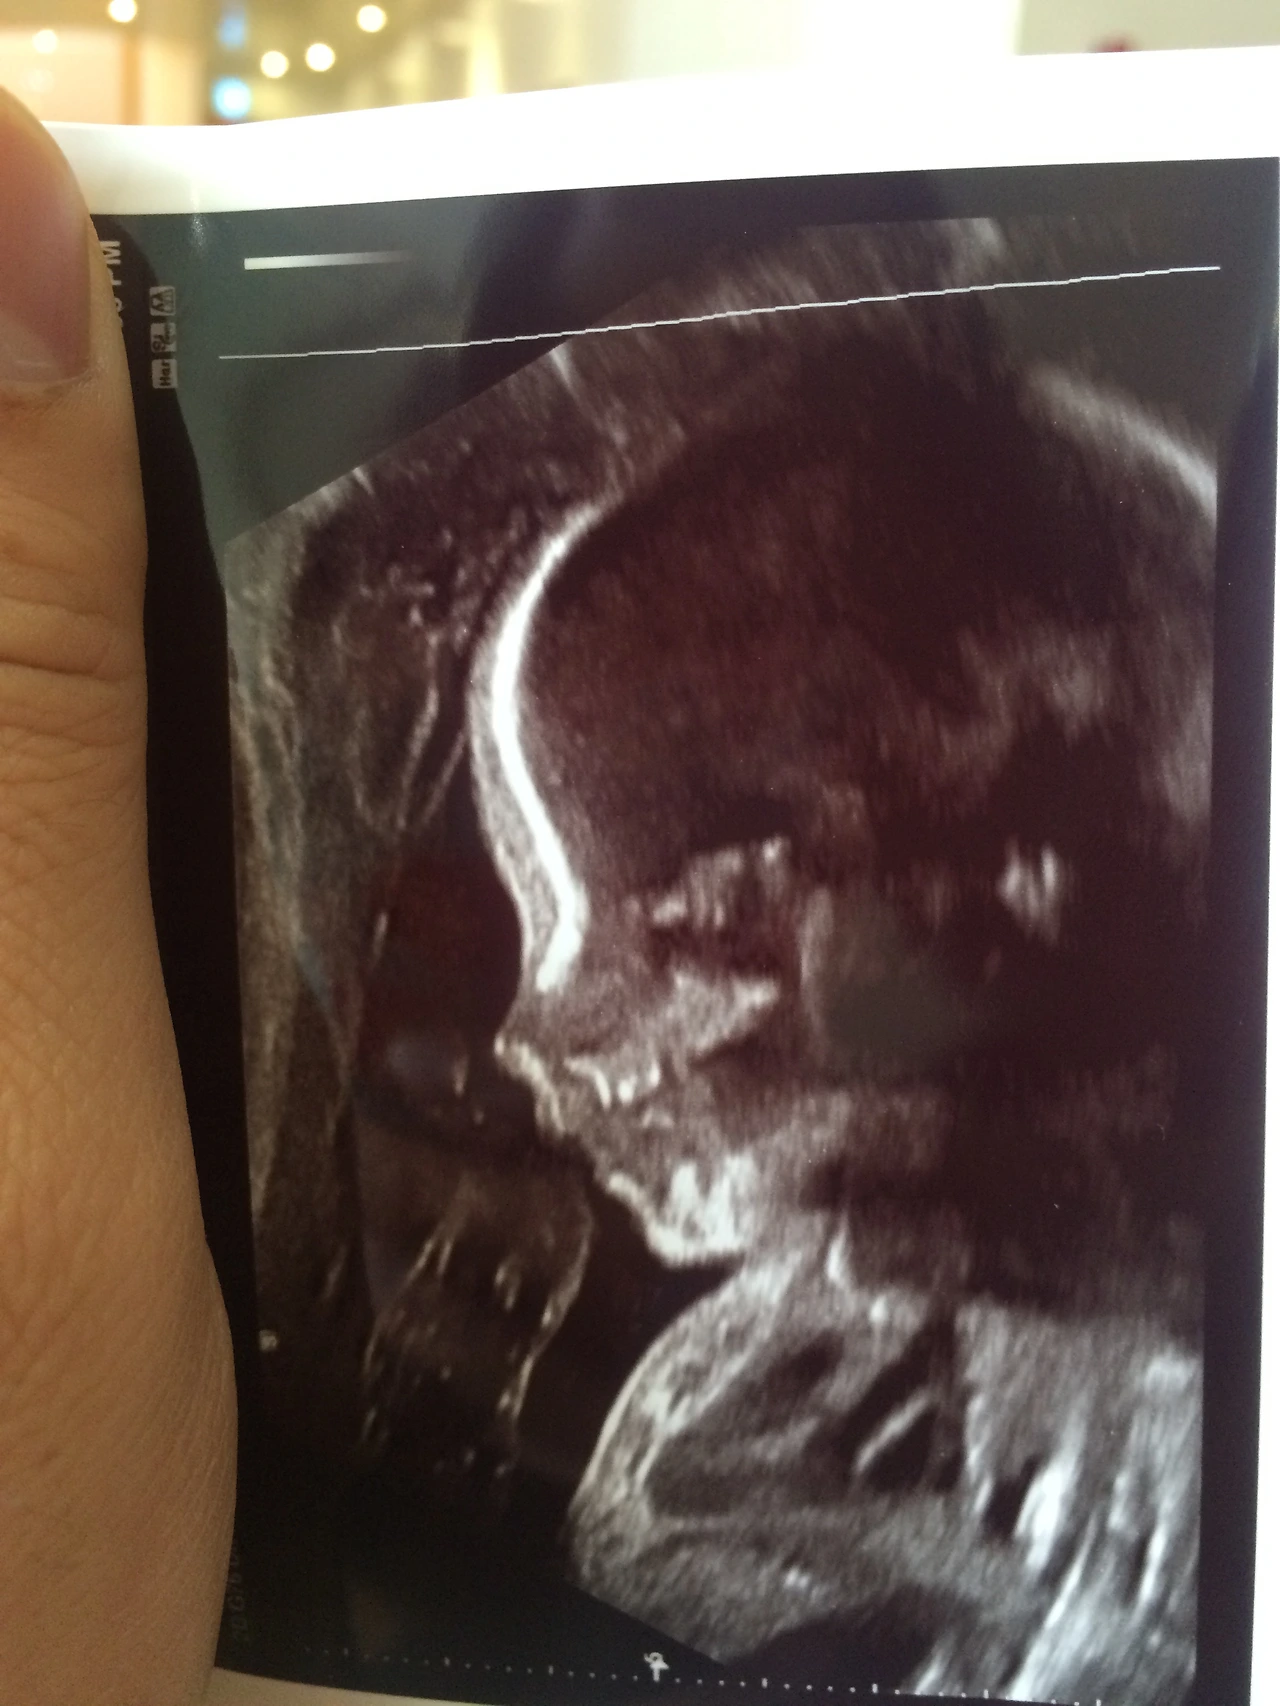

결혼 9년 차, 드디어 기다리던 아기를 임신했다. 그동안 우리 부부는 아기를 기다렸지만 쉽게 임신이 되지 않았다. 그래서인지 임신소식에 말할 수 없이 기뻤다.

배에 손을 올리고는 태명을 불렀다. 별 반응은 없었지만 태명을 부른 나에게는 반응이 있었다. 감격과 감사의 마음이었다. 그저 태명을 불렀을 뿐이지만 확실히 느낄 수 있었다. 생명을 말이다. 생명은 햇살이라는 이름을 가지고 10개월 동안 아내의 뱃속에서 자랄 것이다. 그리고 세상에 생명으로 태어날 것이다.